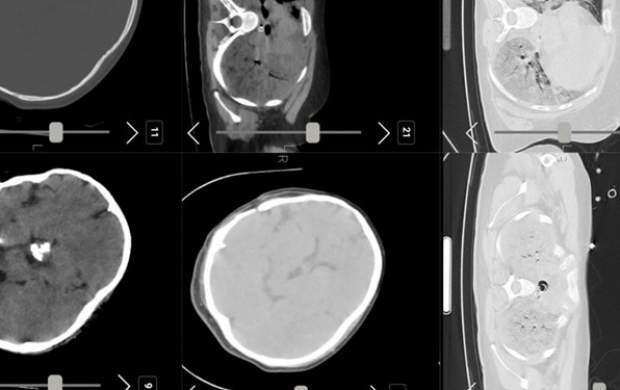

به گزارش پایگاه خبری تحلیلی آوای لطیف :هیأت بورد رادیولوژی درباره تصاویر «سی تی اسکن» منتشر شده از مرحومه مهسا امینی اعلام کرد که هیچ شواهدی از خونریزی مغزی در این تصاویر به چشم نمیخورد.

در بیانیه هیأت بورد رادیولوژی آمده است :«متخصصین نرورادیولژی هیات بورد پس از بررسی تصاویر سی تی اسکن مغز مرحومه مهسا امینی اعلام می دارد در سی تی اسکن که بصورت فیلمبرداری از مانیتور تهیه شده است خونریزی در پارانشیم مغزی، خونریزی اپیدورال و سابدورال دیده نمیشود.

بر اساس این بیانیه، نظریه تکمیلی پس از مشاهده اصل اطلاعات تصویری ارسال خواهد شد.